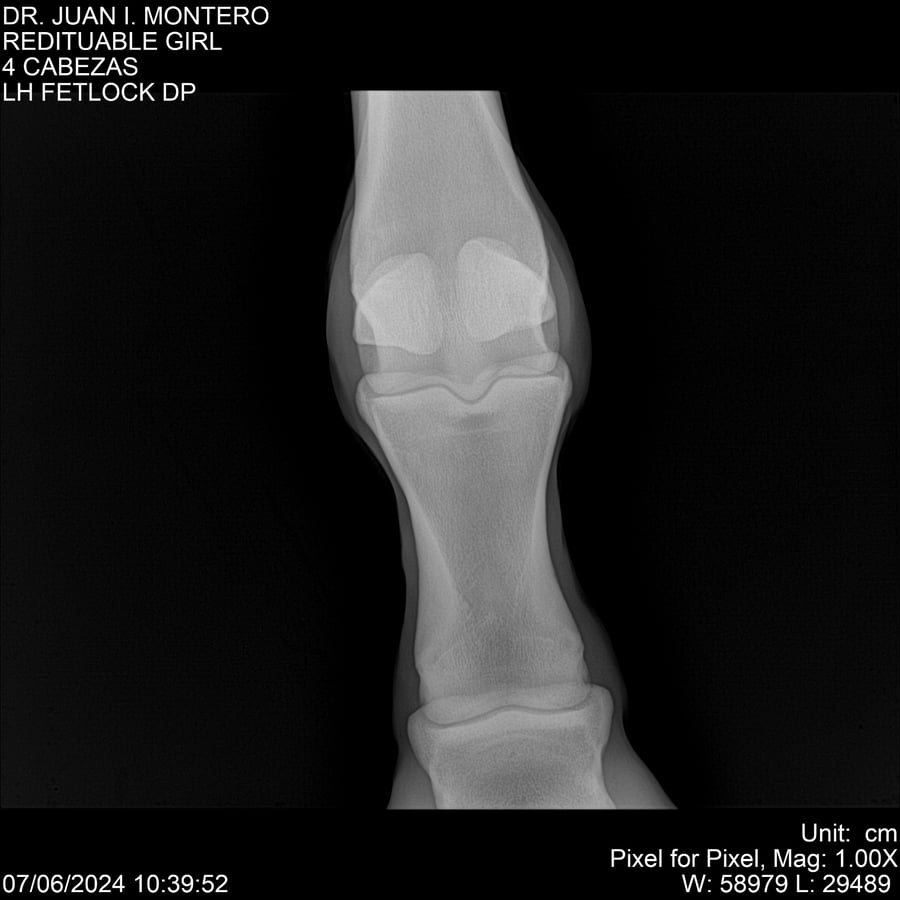

LOTE 19, REDITUABLE GIRL Lote Anterior Volver al remate Lote Siguiente Ficha Contacto Montevideo - Ficha del Lote Identificador: #281096 Categoría: Yeguarizos Montevideo - 79 Visualizaciones ClicData Contacto Empresa: Abelenda N. R., Walter Hugo Nombre*: Teléfono* : E-mail* : Mensaje Enviar Registrese gratis Este contenido Exclusivo está disponible sólo para usuarios registrados Ingresar